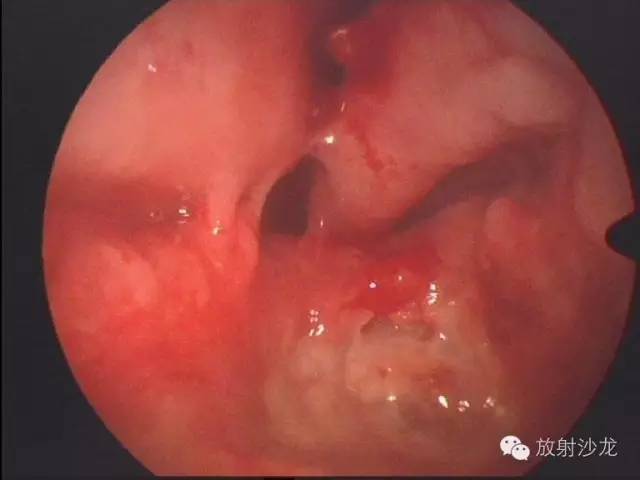

【术中鼻内镜】